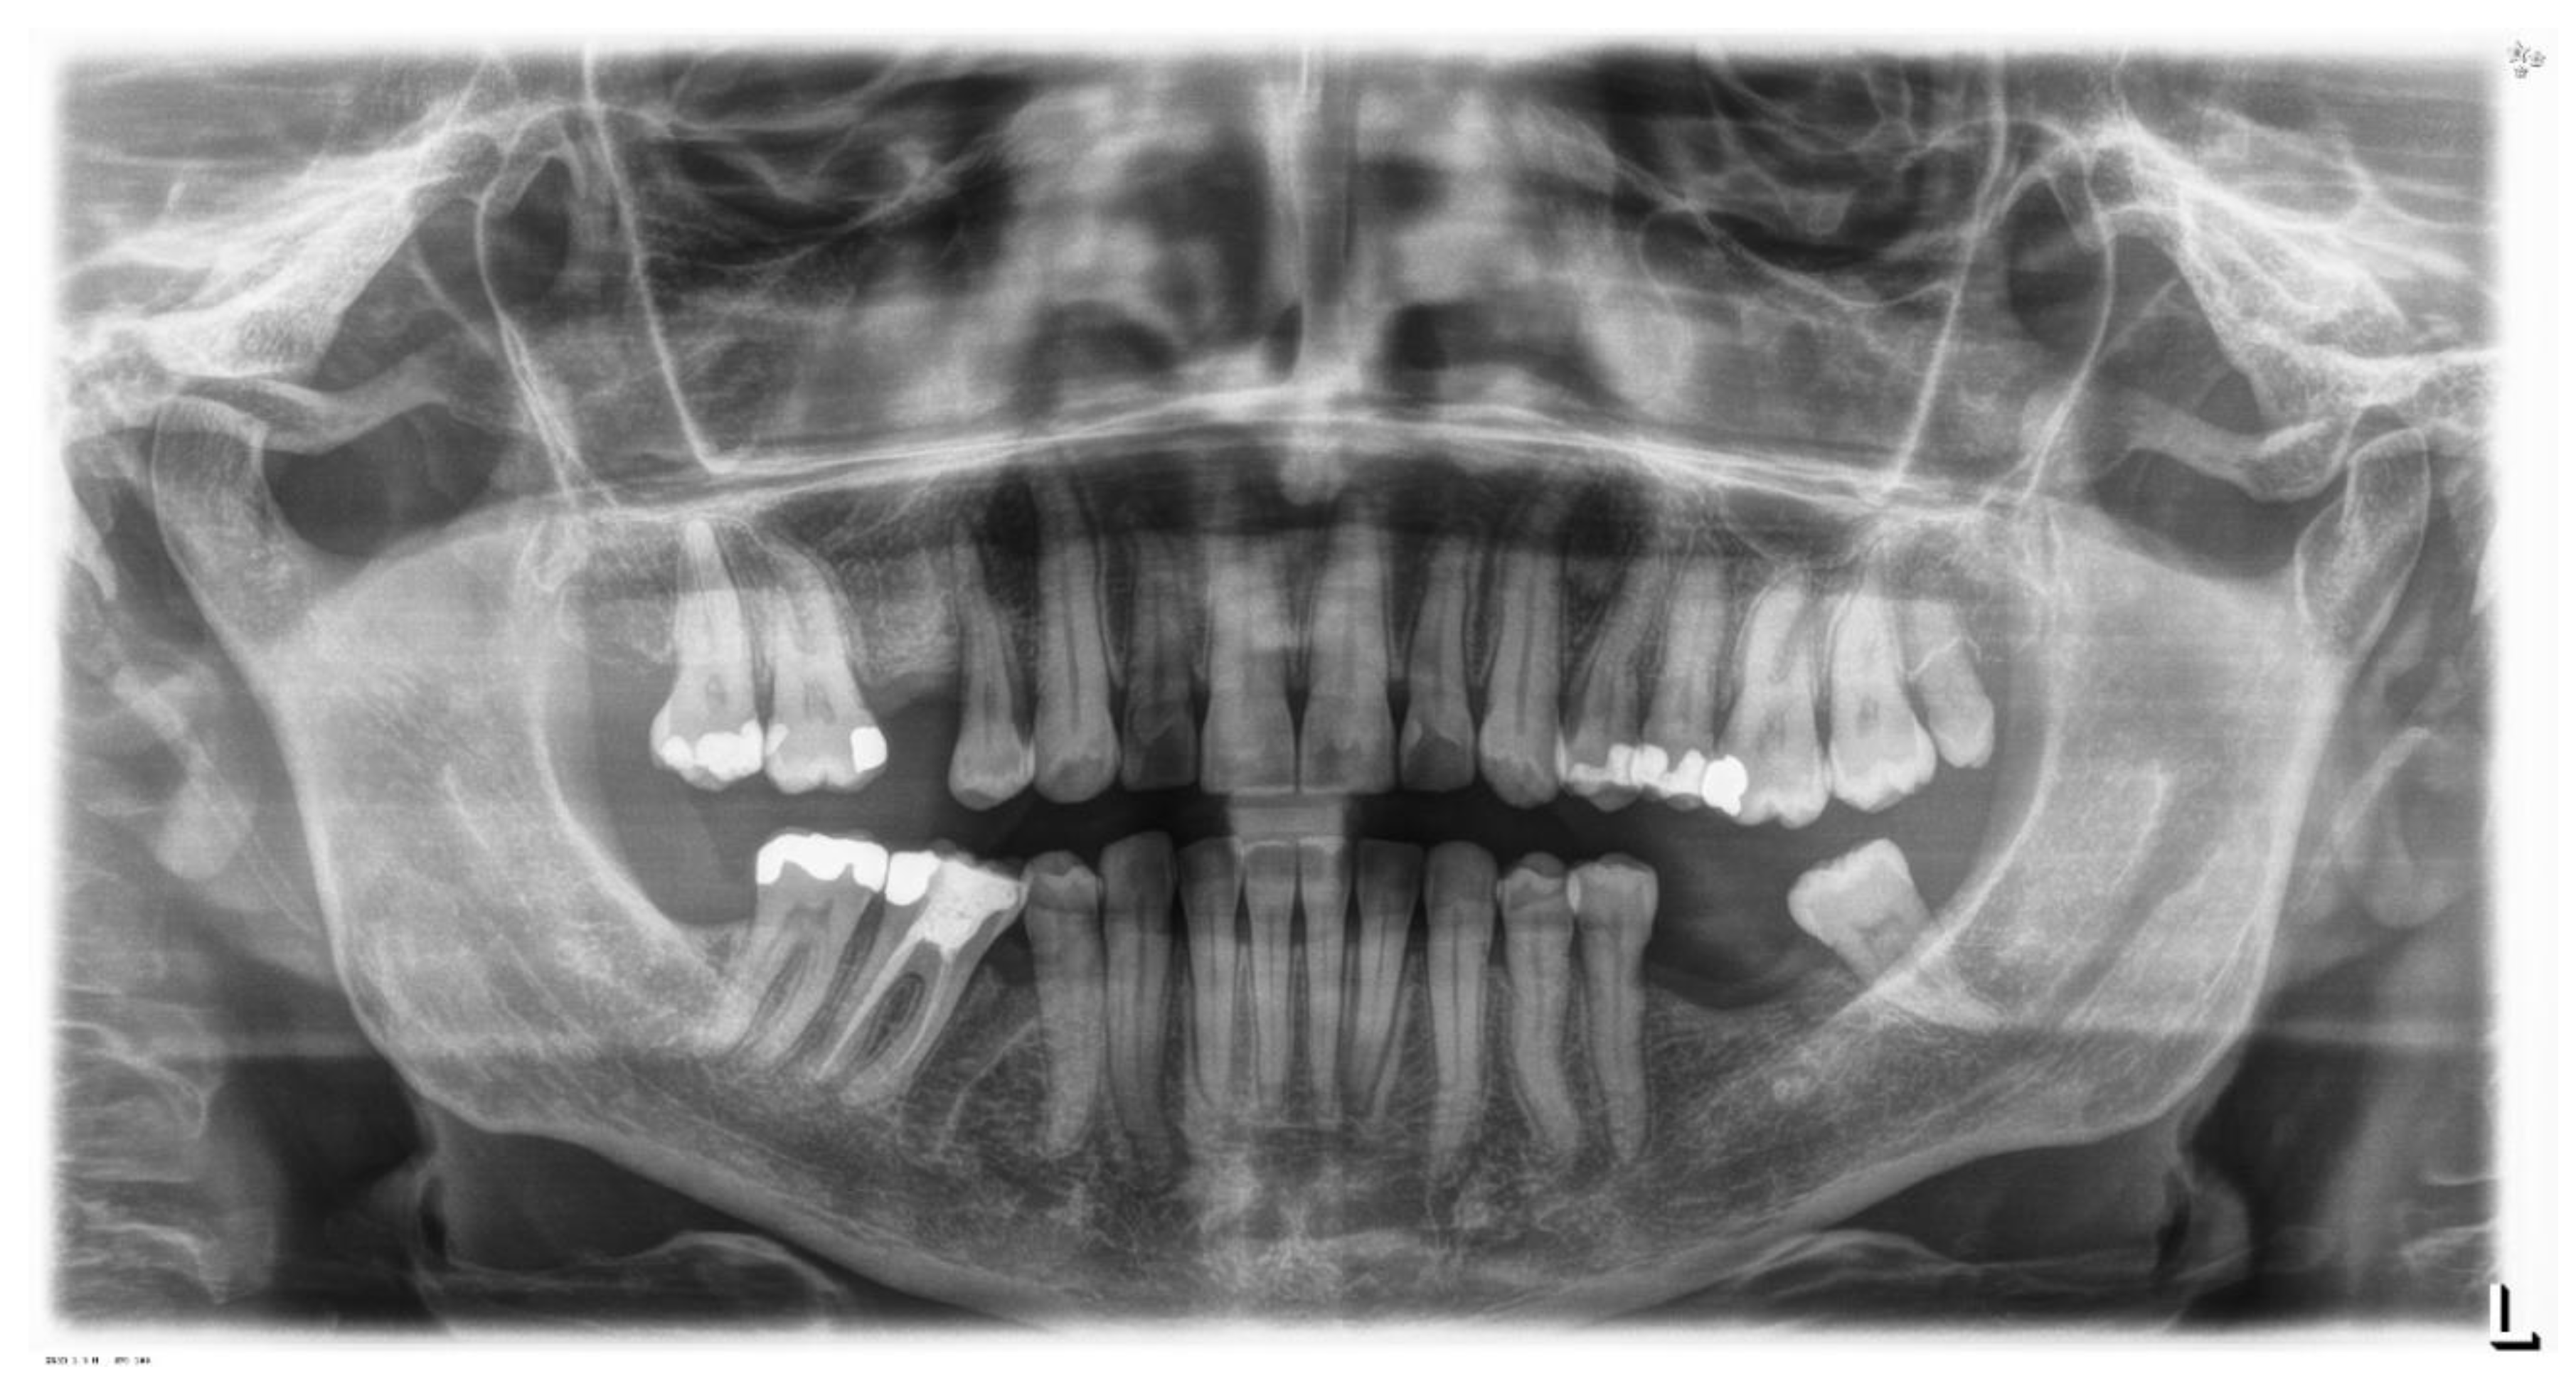

The patient is an 11-year-old female, in late mixed dentition. Clinical examination revealed acceptable oral hygiene, absence of functional anomalies and oral habits, the presence of deciduous molars (5.5 and 6.5), and erupting permanent teeth. The intraoral examination showed a molar and canine Angle class II on both sides, increased overjet, posterior unilateral functional crossbite on the right side, lower/upper midline deviated to the right/left of 2 mm, and increased overbite (5 mm) (Figure 6). The most important problem was that 1.3 was not in the arch, while the contralateral 2.3 had been present for more than 6 months. Diagnostic X-ray confirmed the 1.3 eruption delay. (Figure 7).

The 1.3 delayed eruption was probably due to the 1.4 mesial inclination and the absence of space. The patient, as demonstrated by cephalometric analysis and radiographic examination, was very near the growth peak, indicating the need to begin the treatment to obtain success of the orthodontic therapy.

Figure 7. Pre-treatment Orthopantomography.

Sensors 21 01856 g007